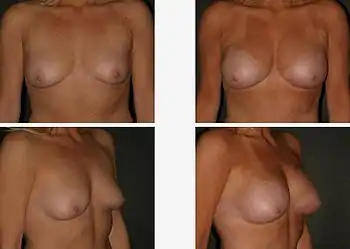

The pre-operative aspects (left), and the post-operative aspects (right) of a bilateral, sub-muscular emplacement of 350 cc saline implants through an infra-mammary fold (IMF) incision | |